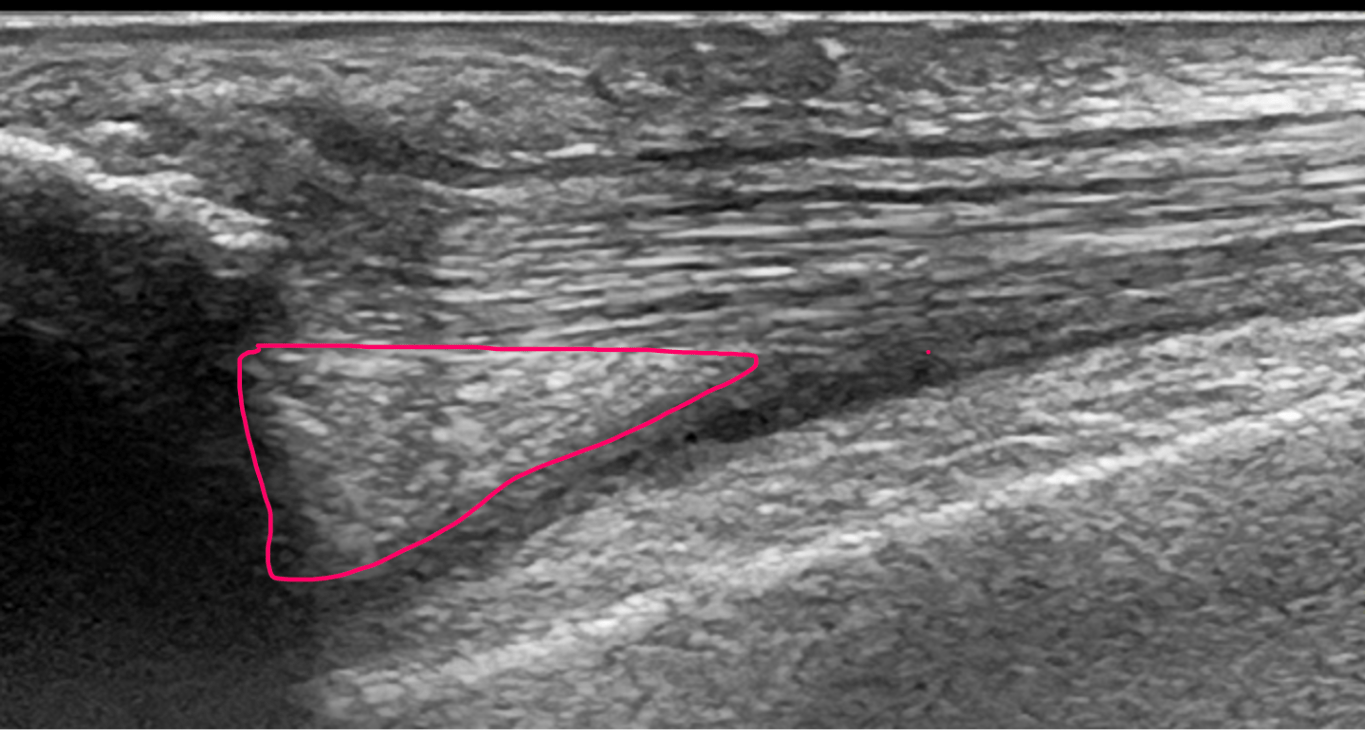

A harbinger of pathology, this finding occurs when a tissue abutting a tear in a tendon or muscle tear drops into the tear.

What is a sag sign?